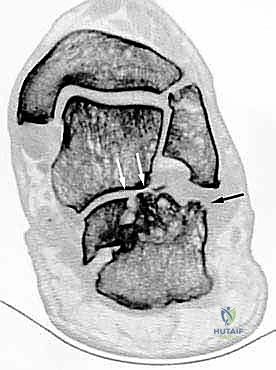

إتقان إعادة بناء سوء التئام عظم الكعب: دليل شامل للمرضى مع الأستاذ الدكتور محمد هطيف

تعرف على سوء التئام عظم الكعب، أسبابه، أعراضه، وكيفية علاجه. الأستاذ الدكتور محمد هطيف، خبير جراحة العظام بصنعاء، يقدم أحدث تقنيات إعادة بن…